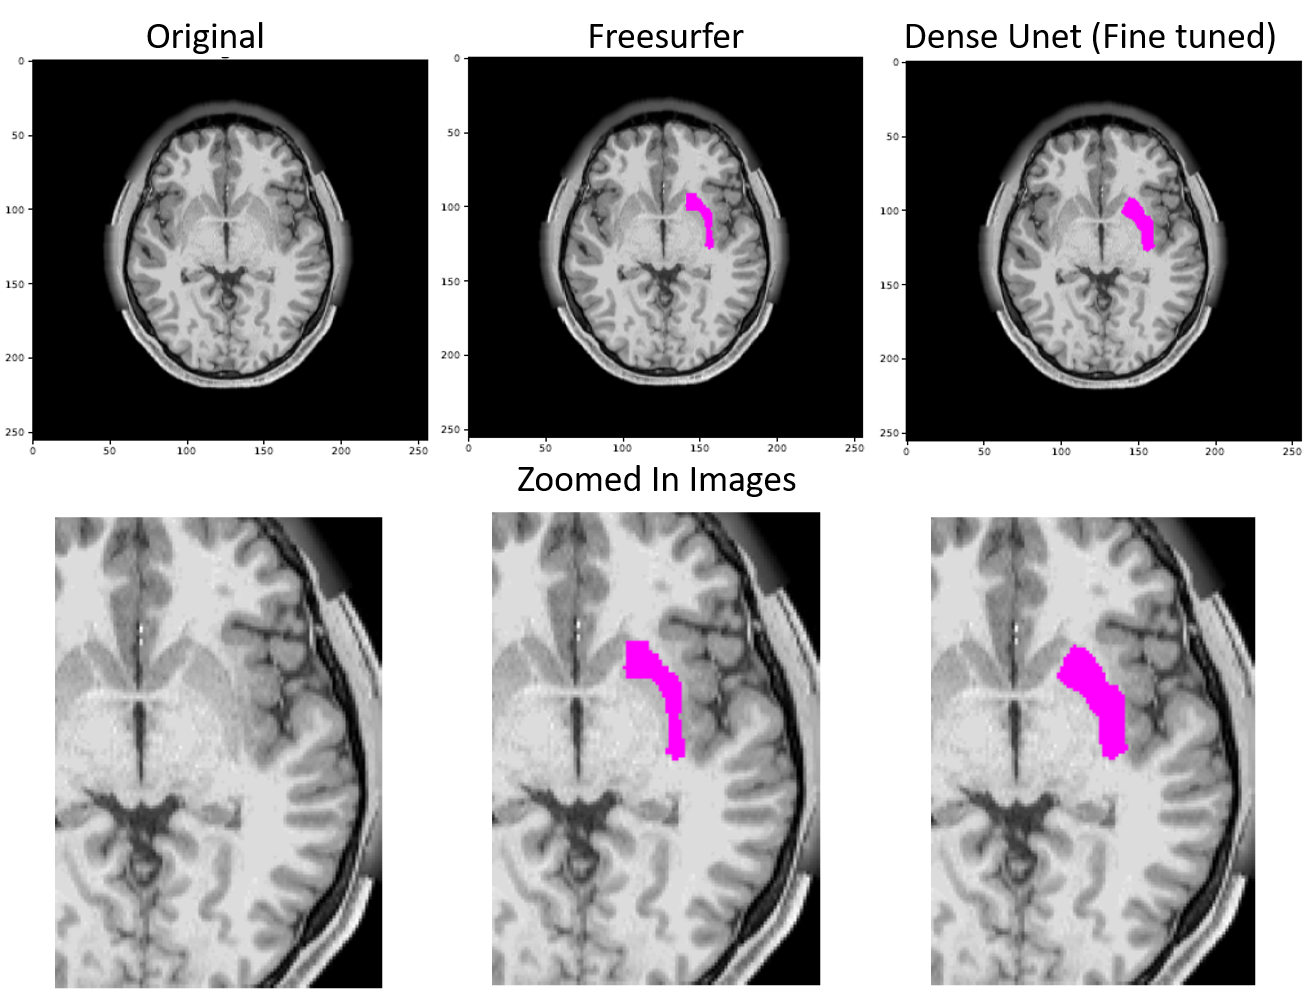

Figure 16 shows the difference in the segmentation outputs of Freesurfer and the proposed model.

Refer to caption

Figure 16: The image shows the original slice of an MRI, Freesurfer’s (FS’s) prediction for Putamen and the proposed model’s prediction of the same. It is evident that FS’s prediction don’t obey the boundaries and are non-natural looking grainy segmentation whereas the proposed model’s prediction obey the segment boundaries and are much more natural looking

Pallidum

Figure 17 shows the difference in the segmentation outputs of Freesurfer and the proposed model.

Figure 17: The image shows the original slice of an MRI, Freesurfer’s (FS’s) prediction for Pallidum and the proposed model’s prediction of the same. It is evident that FS’s prediction don’t obey the boundaries and are non-natural looking grainy segmentation whereas the proposed model’s prediction obey the segment boundaries and are much more natural looking